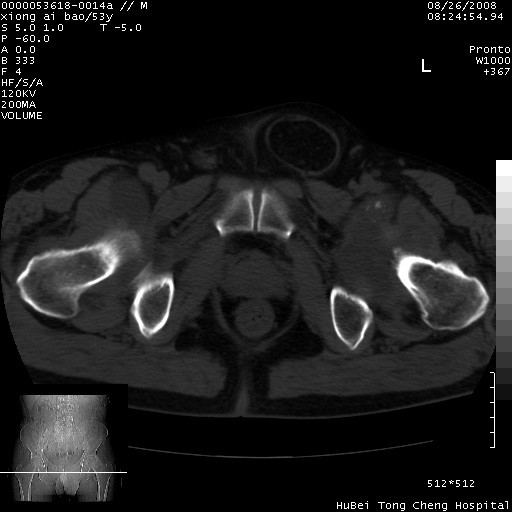

标题: CT15583:M,53Y。请老师指教分析骨盆及其他病变。 [打印本页]

标题: CT15583:M,53Y。请老师指教分析骨盆及其他病变。

股骨头坏死/腹股沟疝。

双侧股骨头无菌坏死,左侧腹股沟斜疝。

非常典型病例,双侧股骨头坏死伴双髋关节周围软组织肿胀,左腹股沟疝。

双侧股骨头坏死伴双髋关节周围软组织肿胀,左腹股沟疝。

双侧骨股头无菌性坏死,左侧腹股沟疝

双侧髋关节肿胀明显,感觉还不能排除结核。

考虑双侧髋关节结核,左侧腹股沟疝